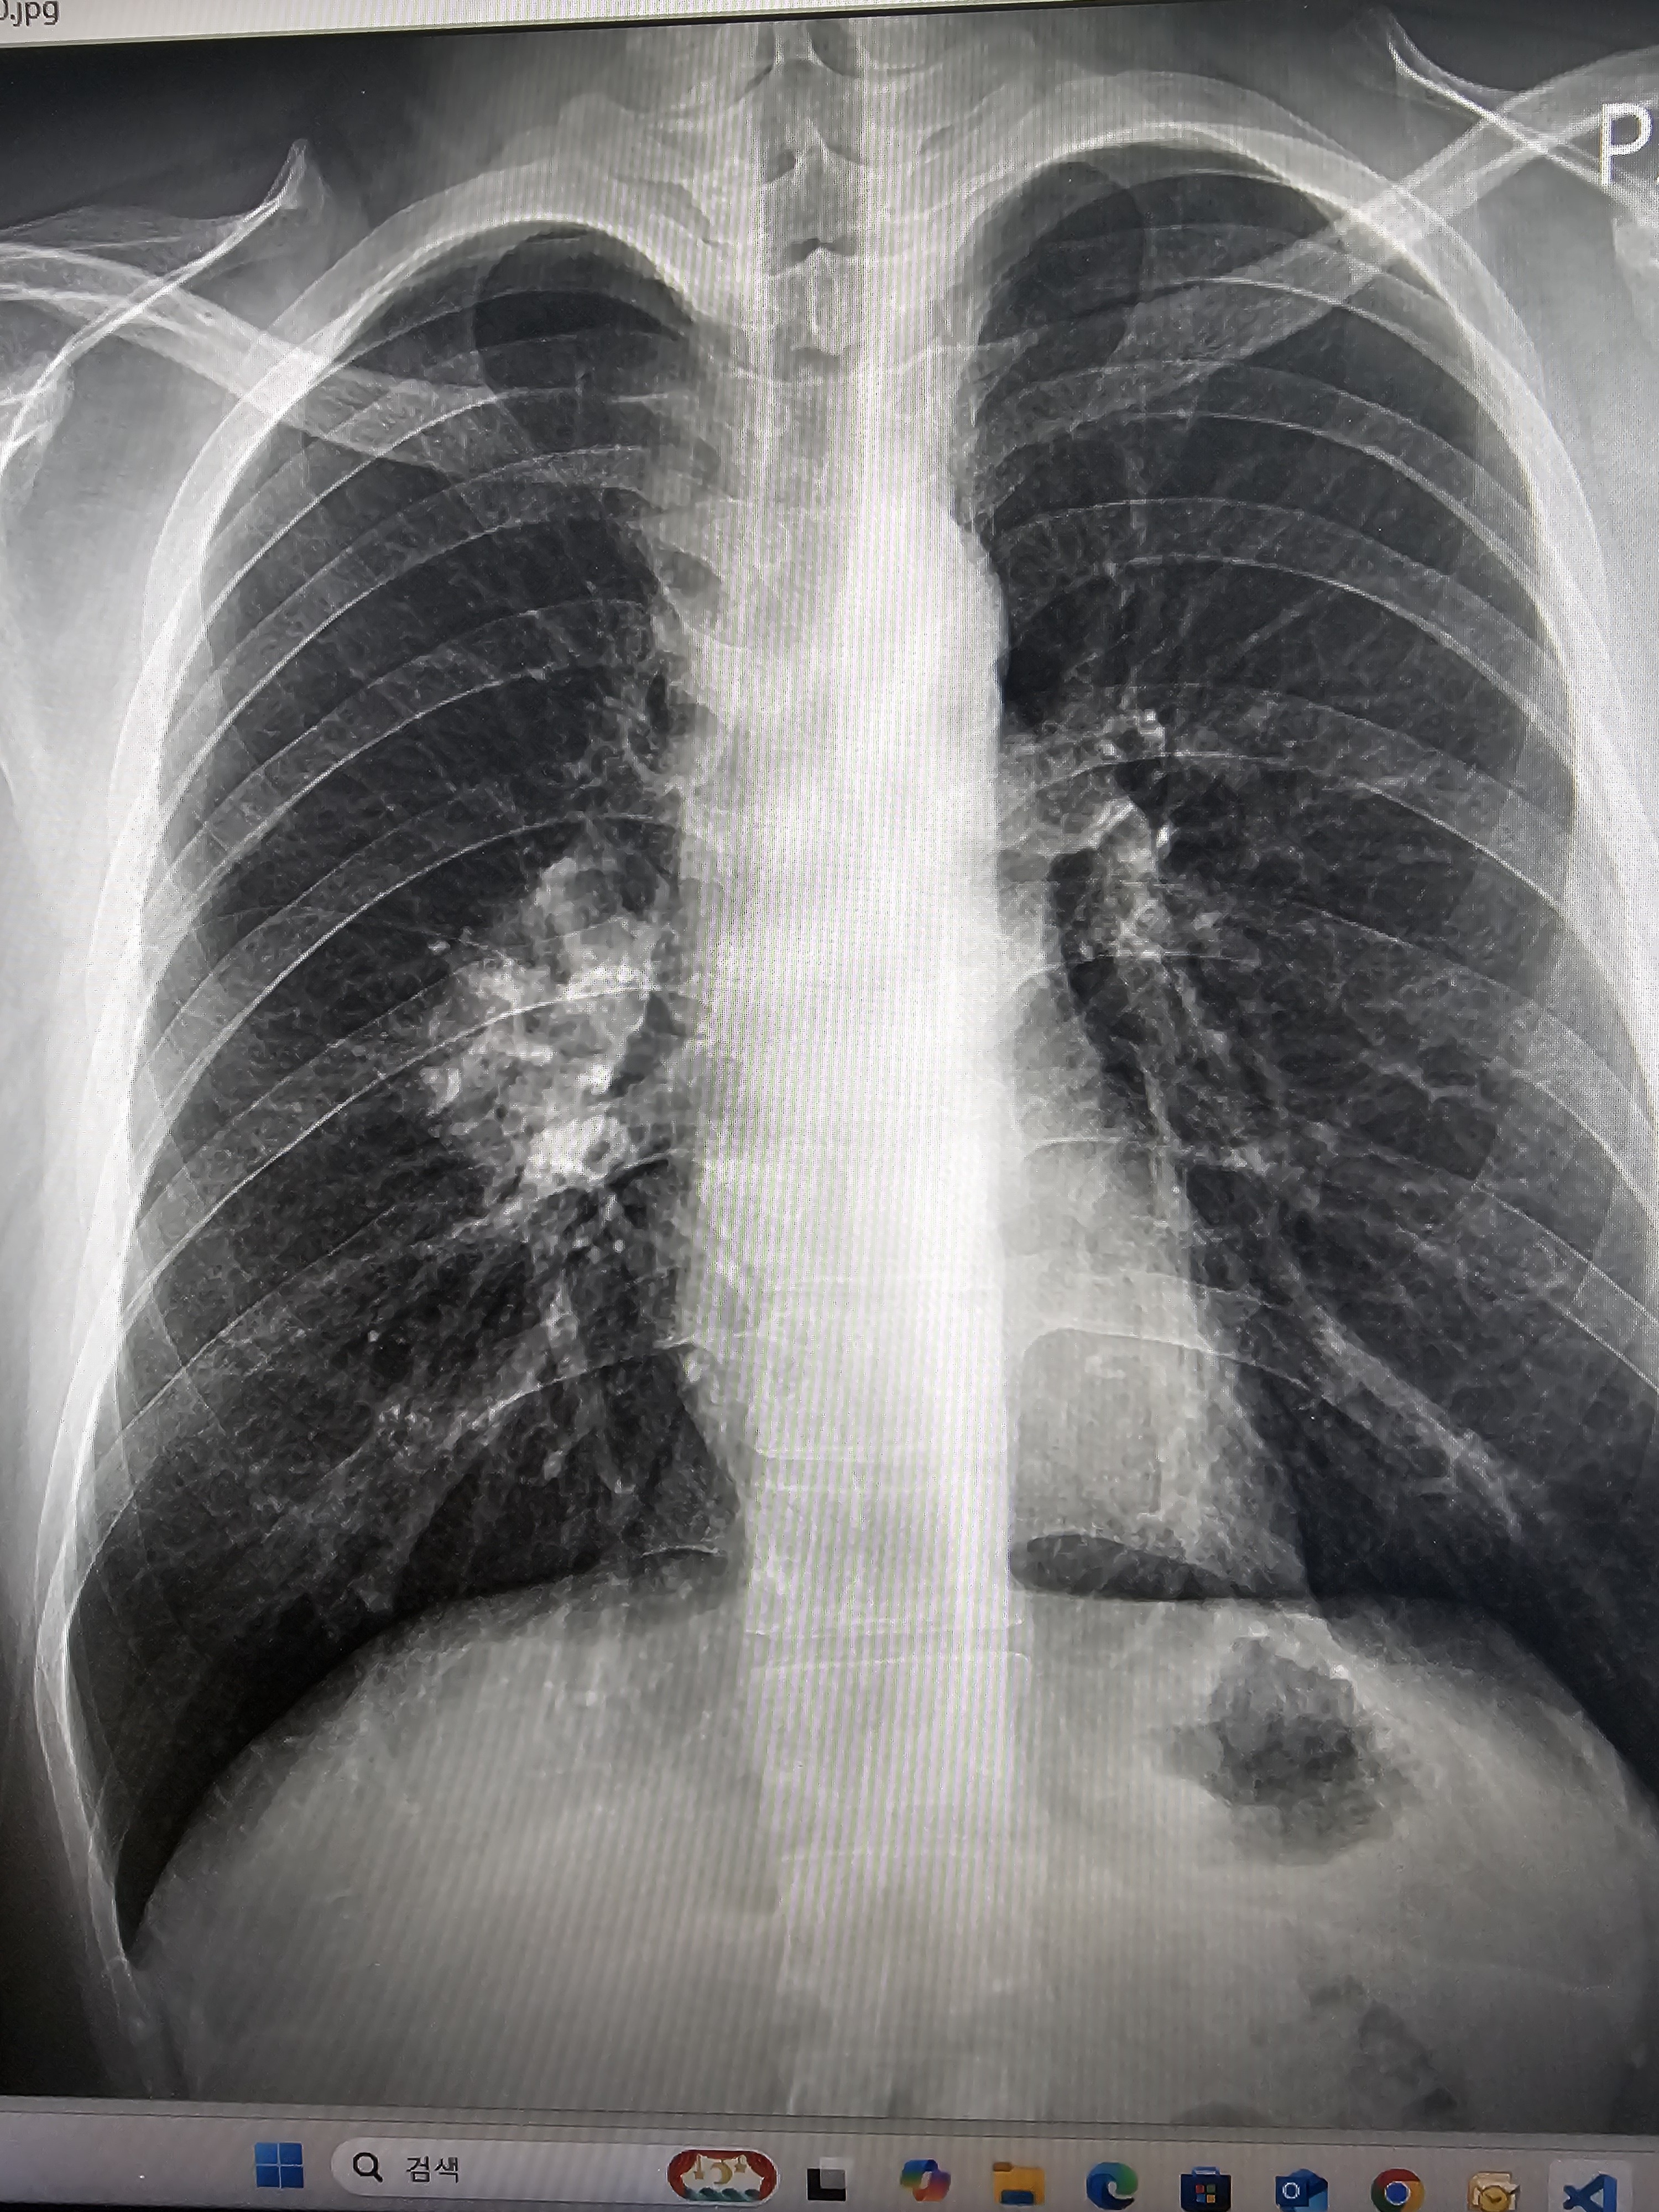

³ªµµ 28»ìÀ̰í È£ÁöŲ ¸²ÇÁÁ¾À¸·Î Ç×¾ÏÄ¡·á Á¾·áÇÑÁö ÀÌÁ¦ 4´Þ µÆ´Âµ¥..

³­ ±¦ÂúÀ»°Å¾ß ÁÁ¾ÆÁú°Å¾ß Æò¼Ò¿¡´Â °è¼Ó »ý°¢Çϸ鼭 Áñ°Ì°í °ÆÁ¤¾øÀÌ »ýȰ ÇÏ´Ù°¡µµ..

ÀÌ·¸°Ô °¡´Â ÀþÀº Ä£±¸µé º¸¸é.. ÀÚ²Ù ¹«¼­¿öÁø´Ù..

¾ÆÁÖ °¡²ûÀÌÁö¸¸.. Àß¶§ ³»ÀÏ ¾ÆÄ§¿¡ ´« ¸ø¶ß¸é ¾î¶±ÇÏÁö Çϸ鼭 Àáµµ Àß ¾È¿Ã¶§µµ ÀÖ°í..

Á¤½Å°ú »ó´ãÀ» ¹Þ¾ÆºÁ¾ßµÇ³ª ¤Ð